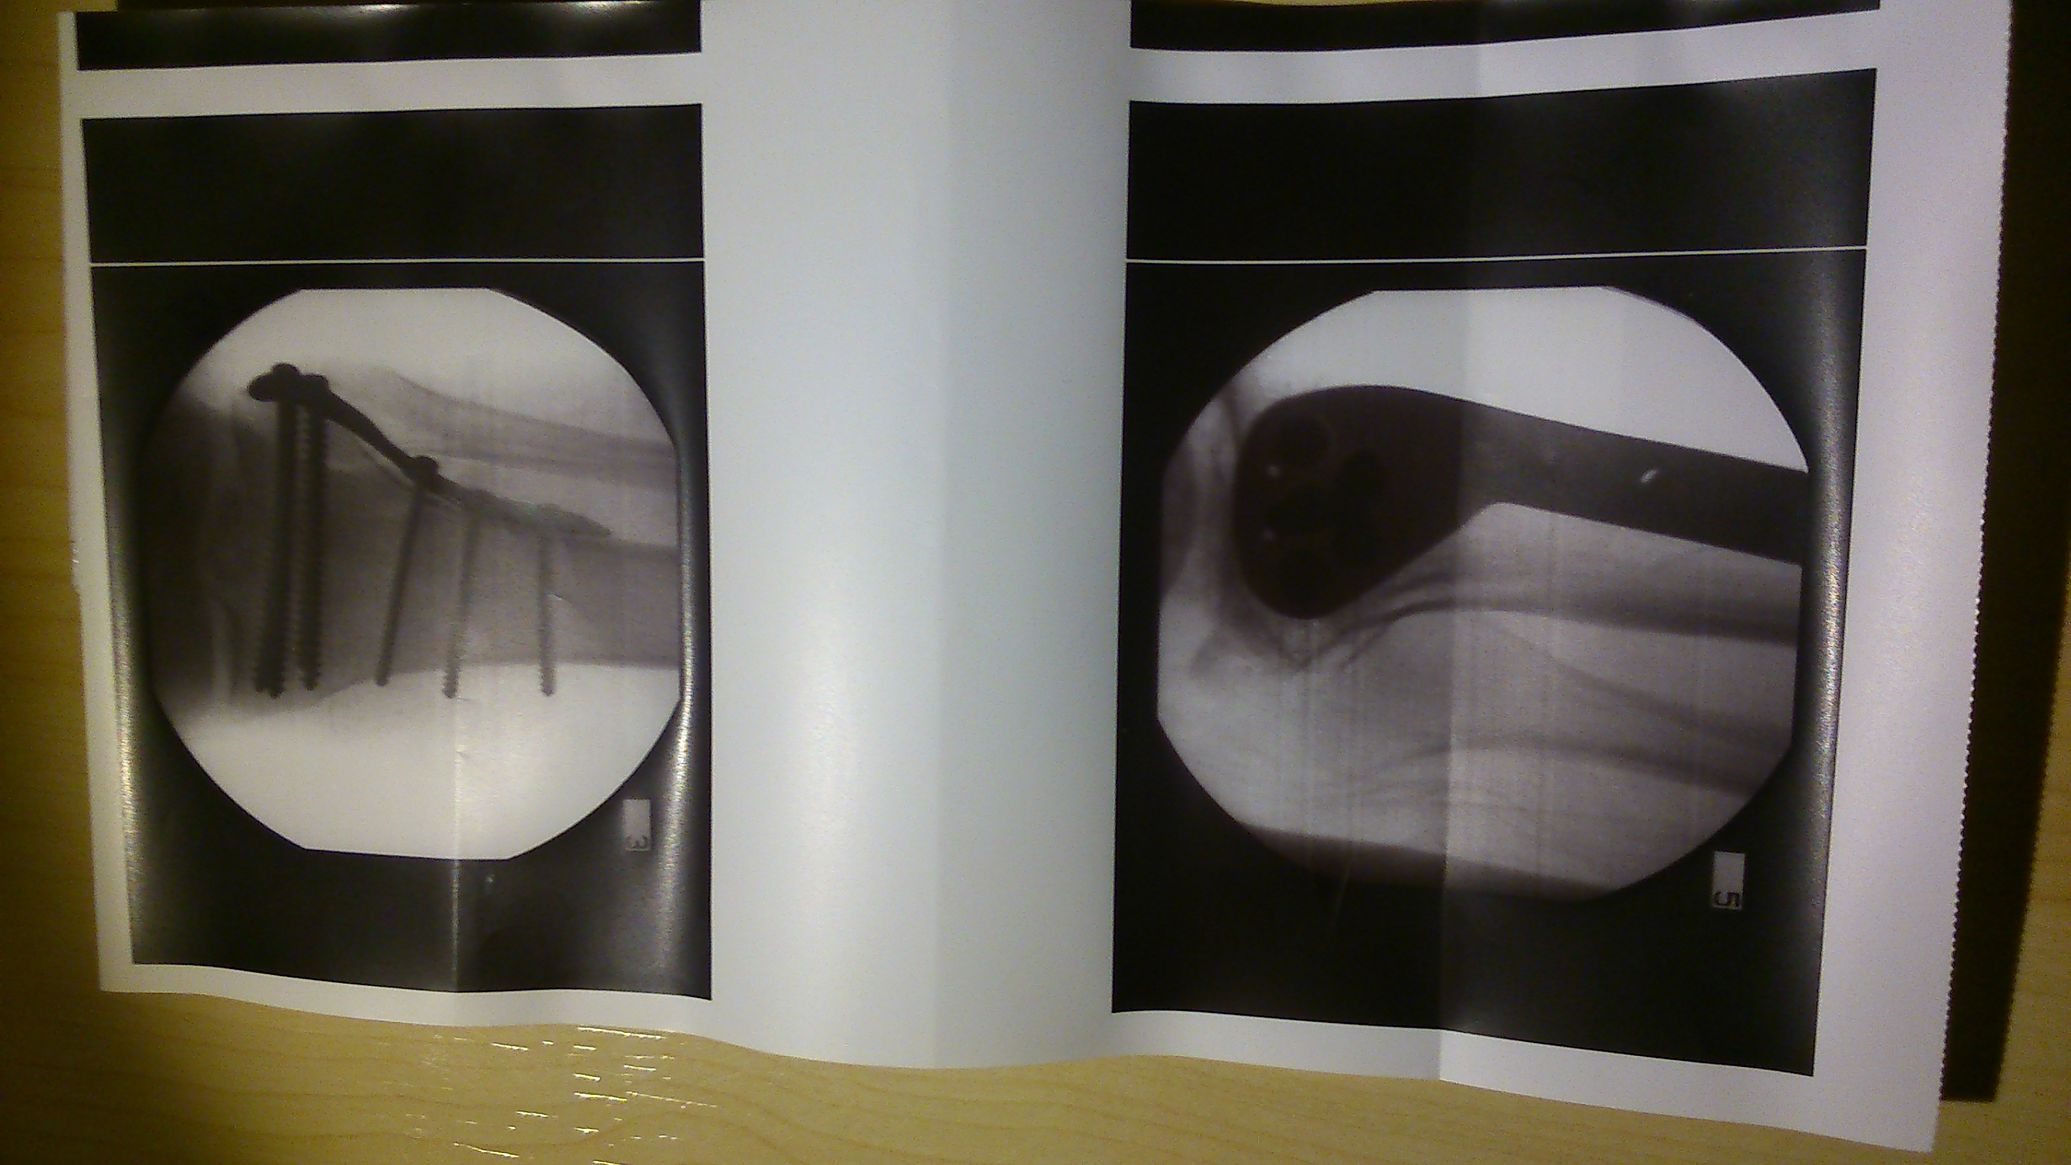

nekem meg még egy röntgenképem sincs az összzcsúszásos kulcscsonttörésemről, amivel dicsekedhetnék

Ezen sok nem látszik,még egy rendes törést sem tudtál összehozni...nem úgy mint ezen.

Igen seggre ültem és a kezem nem tudott csillapítani. A Mindenható velem volt, mikor gyerek voltam egy utcai verekedés után a kezem feldagadt a röntgen orvos azt mondta hogy nekem soha nem fog csontom törni, akkor még feljártam a hegyre és volt izom a hátamban ami megtartotta a gerincet. De mindenképpen a szerencse. A többit nem meséltem mert senki nem hinné el amit mondok.